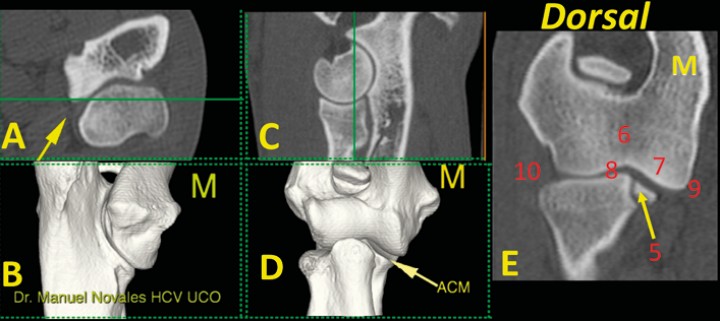

<p>Codo normal. Imágenes tridimensionales del codo en visión caudomedial (<strong>B</strong>) y craneal (<strong>D</strong>), así como planos de corte transversal (<strong>A</strong>), sagital (<strong>C</strong>) y dorsal (<strong>E</strong>). Las líneas verdes en A y C muestran el nivel al que se ha producido el plano dorsal (E). Se señala el ápex de la ACM (flecha amarilla). En este plano dorsal se valora: ACM (mediante avance del corte dorsal para valorar una posible línea de fragmentación) (5); la unión de las dos porciones del cóndilo humeral (6); la morfología normal del hueso subcondral de la porción medial del cóndilo del húmero y su grado de opacidad (7); la amplitud de los espacios articulares humero-radial y húmero-cubital (8); la ausencia de osteofitos o enteseofitos en las caras medial (9) o lateral (10) del codo. (M: lado medial).</p>

Figura 9

Codo normal. Imágenes tridimensionales del codo en visión caudomedial (B) y craneal (D), así como planos de corte transversal (A), sagital (C) y dorsal (E). Las líneas verdes en A y C muestran el nivel al que se ha producido el plano dorsal (E). Se señala el ápex de la ACM (flecha amarilla). En este plano dorsal se valora: ACM (mediante avance del corte dorsal para valorar una posible línea de fragmentación) (5); la unión de las dos porciones del cóndilo humeral (6); la morfología normal del hueso subcondral de la porción medial del cóndilo del húmero y su grado de opacidad (7); la amplitud de los espacios articulares humero-radial y húmero-cubital (8); la ausencia de osteofitos o enteseofitos en las caras medial (9) o lateral (10) del codo. (M: lado medial).

En el plano dorsal nos fijamos en tres zonas de corte concretas: a) la escotadura troclear del cúbito (Fig. 6); b) el ápex de la ACM, que debe ser cóncavo por su cara medial (Fig. 7); y c) la base de la ACM (Fig. 8). En este plano de corte debemos valorar: 5) ACM (mediante avance del corte dorsal para valorar una posible línea de fragmentación); 6) la unión completa de las caras medial y lateral del cóndilo humeral en su zona media; 7) la morfología normal del hueso subcondral del cóndilo humeral y su grado de esclerosis; 8) la congruencia articular humero-radial y húmero cubital; 9 y 10) y la ausencia de osteofitos o enteseofitos en las caras medial y lateral del codo (Figs. 7, 8 y 9) (Vídeo 3).